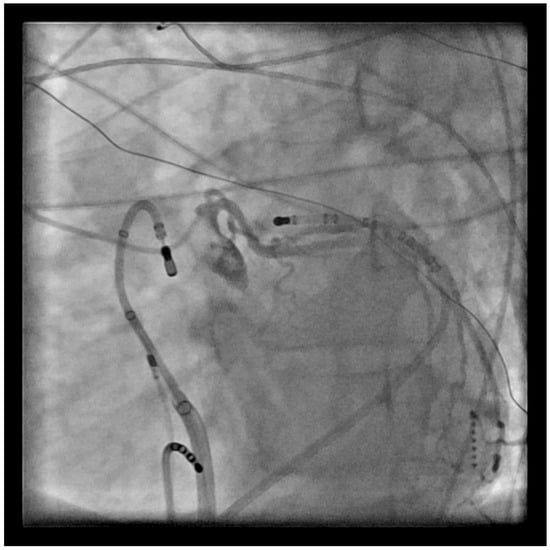

2.2. Catheter Ablation

4.2. Catheter Ablation

5.2. Catheter Ablation Considerations

6.2. Catheter Ablation